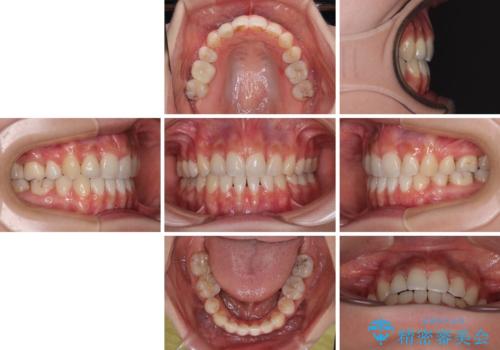

下顎の抜歯位置を左右で変えることで、最終的に上下正中をほぼ一致させることができました。

また上顎前歯は大臼歯に補綴治療が必要であったため、矯正治療後にオールセラミッククラウンによる補綴治療を行うこととしました。